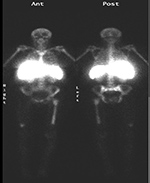

Figure 35A Figure 35B

PA Chest radiograph (A) demonstrates a sternal cage. Whole body Tc99m MDP images (B) demonstrate focal radiotracer activity in ribs bilaterally on the anterior view representing the sites of sternal cage fixation with bony reaction.